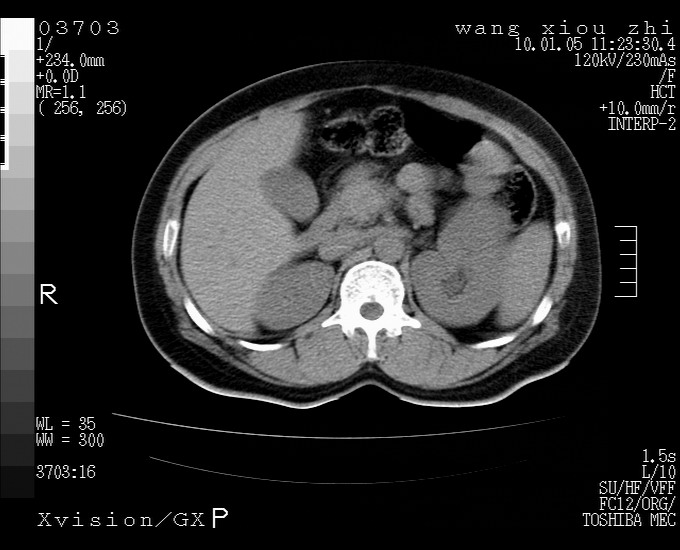

标题: CT23996:f,40.B超提示肿物。 [打印本页]

标题: CT23996:f,40.B超提示肿物。

左肾体积增大!下极见一密度略高团状软组织影!肾周结构组织未见明显异常!考虑左肾占位!建议增强!病史?

左肾占位,肾门及腹膜后淋巴结肿大,考虑透明细胞癌可能性大,建议增强

左肾体积增大,内见肿块影,考虑占位,建议增强。